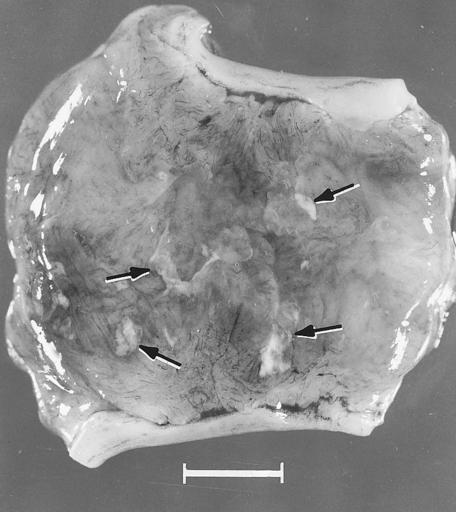

MAKE A MEME View Large Image Diseases of Swine 17-5.png en 17 5 Segment of uterus opened to show necrotic remnants of a partially resorbed PPV-infected embryo arrows and associated extraembryonic membranes of a gilt experimentally infected oronasally immediately after ...

Keywords: Diseases of Swine 17-5.png en 17 5 Segment of uterus opened to show necrotic remnants of a partially resorbed PPV-infected embryo arrows and associated extraembryonic membranes of a gilt experimentally infected oronasally immediately after breeding and killed 22 days later; remnants are laden with virus and viral antigen Bar 1 cm Mengeling et al 1980a Diseases of Swine 8th edition W L Mengeling W L Mengeling According to its copyright statement Copyright is not claimed for Chapters 17 23 25 31 and 64 which are in the public domain Diseases and disorders of pigs